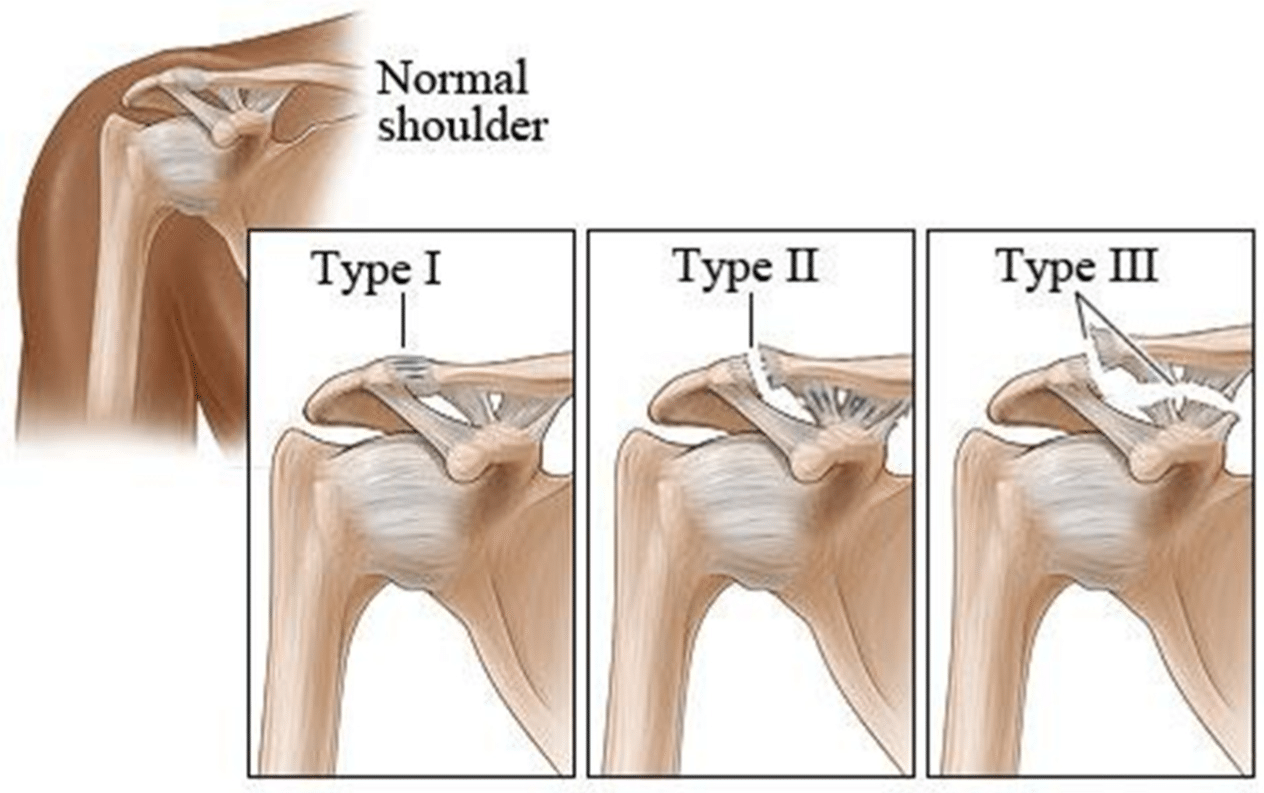

AC Joint Injuries

Injury to the joint at the top of the shoulder.